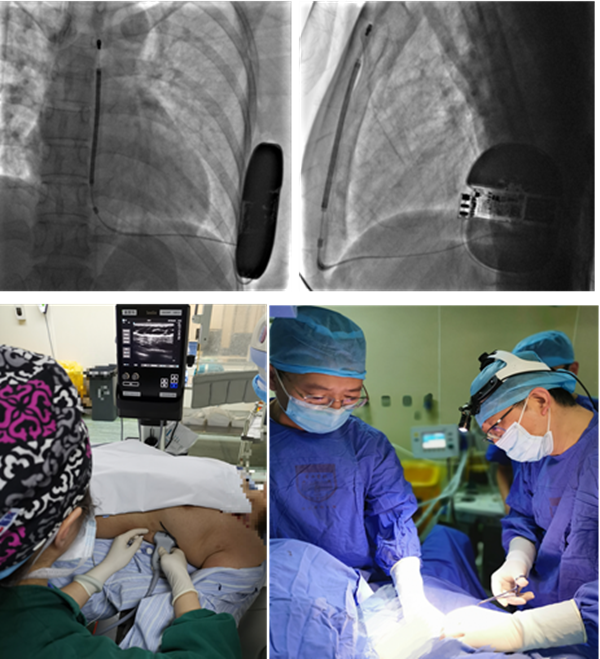

左3:陈刚,左4:朱军,右3:金波,右4:郁文 3月8日,在华山医院心内科主任施海明教授的大力支持和协调下,心内科朱军副主任医师团队与胸心外科陈刚副主任医师、麻醉科郁文副主任医师合作,在华山北院成功为一名38岁的心脏性猝死女性患者陈女士(化名)植入全皮下植入式心律转复除颤器(S-ICD)。经前锯肌阻滞麻醉镇痛法的S-ICD植入是上海市首例。 2月18日凌晨,陈女士生气后突发意识不清、四肢抽搐大小便失禁等症状,家人呼之不应,持续数分钟后恢复意识,诉心悸不适。外院心电图显示:阵发性室性心动过速。转诊至华山北院心内科门诊,结合陈女士无猝死家族史,医生拟诊为阵发性室性心动过速伴阿斯综合征,收治入院后确诊为阵发性室性心动过速心脏性猝死。考虑到陈女士为心脏猝死二级预防患者,符合植入式心律转复除颤器(ICD)的I类适应证。在完善了术前准备后,医疗团队默契配合,采用前锯肌阻滞麻醉镇痛法,历时1.5个小时,顺利植入S-ICD。陈女士术后即可下床,出院前对医护团队表示最深的感谢和敬意。

术中

近年来,权威数据显示,每年约54.4万人发生心脏性猝死,且这个数据在不断增加。植入埋藏式心脏转复除颤器(ICD)是目前唯一能预防心脏性猝死的有效方法。但是传统的经静脉埋藏式心脏转复除颤器(TV-ICD),需导线进入心脏,在多年使用后,会发生静脉闭锁,导线电极断裂、功能毁损,瓣膜关闭不全,心内膜炎等情况,更换拔出也具有很大的手术风险,与导线相关的并发症高达79%。 全皮下转复除颤器(S-ICD)的导线埋在胸前肌肉下面,即使长期使用,功能损毁的风险也较低,如将来需要取出,处于皮下的手术位置也会极大降低风险,因此成为以下患者预防猝死的首选:当前或预计无需起搏的患者;不超过65岁、生活状态积极的患者;无静脉通路的患者;遗传性离子通道病患者;植入TV-ICD有高风险并发症的患者;有高风险发生感染(糖尿病、血透、使用免疫抑制剂、肾病)或有心内膜炎病史的患者;年轻女性、对上胸部美观有要求者。 S-ICD植入的麻醉方式多采用气管插管式的全身麻醉或者局部麻醉,局麻方式患者疼痛感较明显。此次手术创新性采用经前锯肌阻滞麻醉镇痛,既缓解了疼痛,又避免了全麻插管。 首次经前锯肌阻滞麻醉镇痛法S-ICD植入术的顺利完成是多学科通力合作的结果,标志着上海对心脏性猝死患者将提供更优质的医疗服务。 |